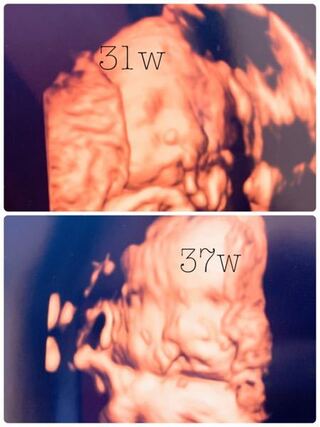

妊娠 37w

37w 6 13w Linenita